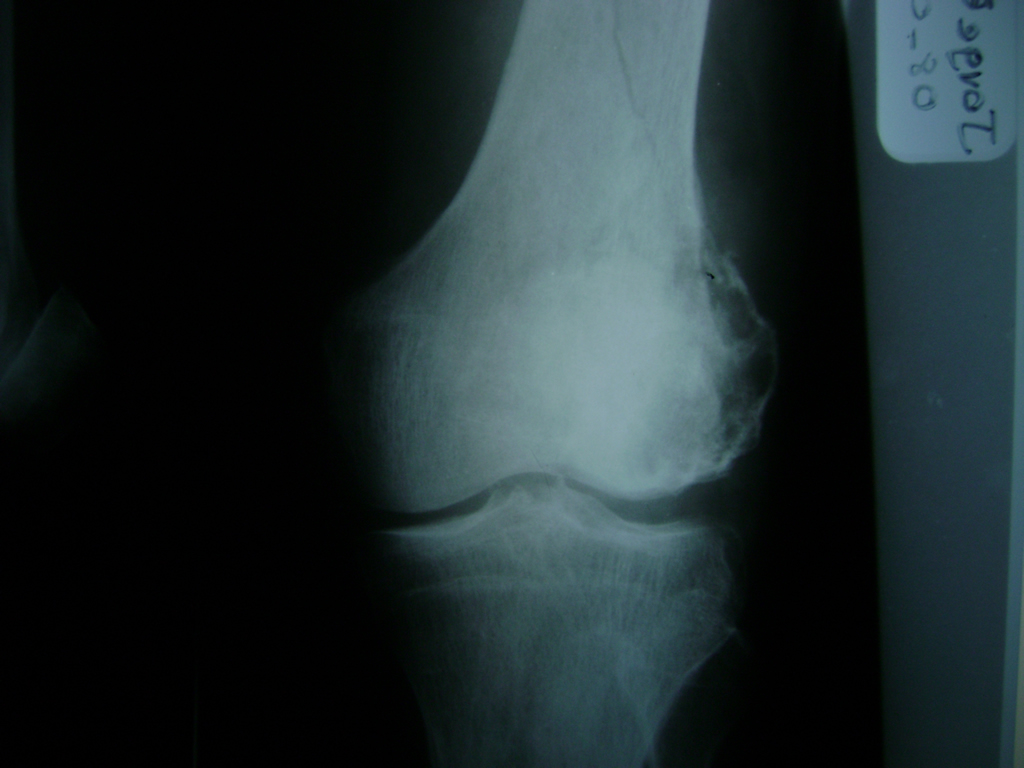

Cirugías de Peroné y Tibia

La artroscopia de rodilla es un cirugía en el cual la estructura interna de la articulación es examinada ya sea para realizar un diagnostico o para realizar un tratamiento, este procedimiento se realiza utilizando un instrumento parecido a un pequeño tubo llamado artroscopio.